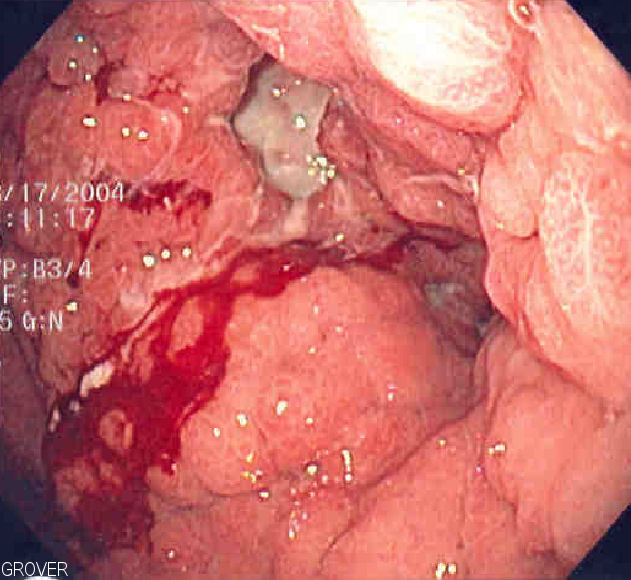

Gastric Carcinoma

Gastric carcinoma is the malignant proliferation of surface epithelial cells (adenocarcinoma) in the stomach.

Gastric carcinoma is sub-categorized as:

- Diffuse

- Intestinal forms

Laparoscopy of gastric carcinomas typically show a big, uneven ulcer with heaped-up edges characterizes the intestinal kind, which is more prevalent.

Gastric carcinoma typically affects the smaller curvature of the antrum (similar to gastric ulcer).

Risk factors for gastric carcinoma include:

- Intestinal metaplasia (from H. pylori and/or autoimmune gastritis)

- Consumption of nitrosamines in smoked foods (common in Japan)

Symptoms of gastric carcinoma include:

- Abdominal pain

- Fatigue

- Weight loss

- Early satiety

- Anemia

Metastasis of gastric carcinoma may affect the left supraclavicular node (Virchow node).

The liver is the site of distant metastasis of gastric carcinoma most frequently.

Intestinal gastric carcinoma commonly affects the periumbilical area (Sister Mary Joseph nodule).

Diffuse gastric carcinoma may involve the ovaries (Krukenberg tumor).